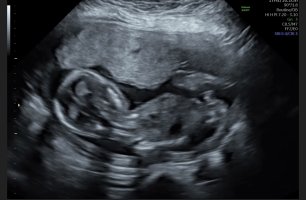

Åå, så kjedelig med dårlige bilder :/.. Jeg har dette også, men her ser man heller ikke stort. Jordmor sa ingenting om hva hun trodde eller noe som helst om kjønnet..Disse bildene var veldig dårlig til å være 14 uker. har du flere fra denne eller tidligere? burde være lett å se kjønn når man er så langt på vei. det på bilde nr 1 er ikke nub, det er en del av benet som har kommet med på bildet. Jeg tror det er jente da det ville vært veldig synlig i uke 14 om det var gutt. Ser og lang hvit strek på flere av bildene som samsvarer med jentenub.